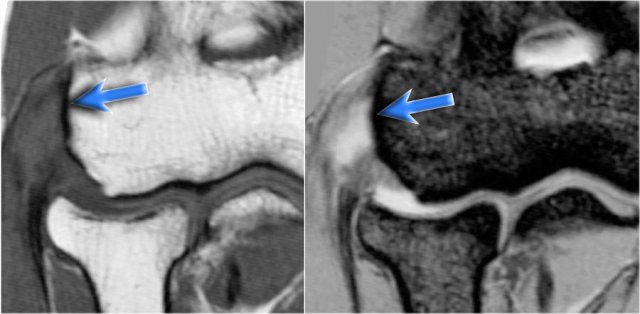

On the coronal images there is a beautiful anterior bundle of the UCL, but notice that there is osteophyte formation on the medial part of the joint (red arrow).

As we go further posteriorly there is a small area of low signal intensity (yellow arrow), which is an avulsion of part of the UCL.

This is better appreciated on the radiograph.

Continue with the axial scan.

As we look on the axial scan, we can appreciate the huge osteophyte formation.

Notice that the ulnar nerve (blue arrow) is next to these osteophytes and these patients may present with ulnar neuropathy.